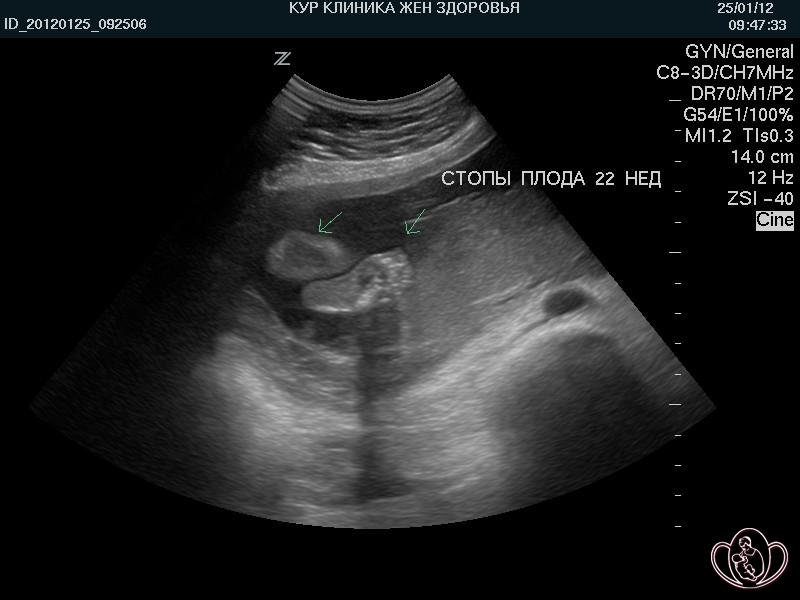

Важный этап: развитие малыша на 20-й неделе беременности